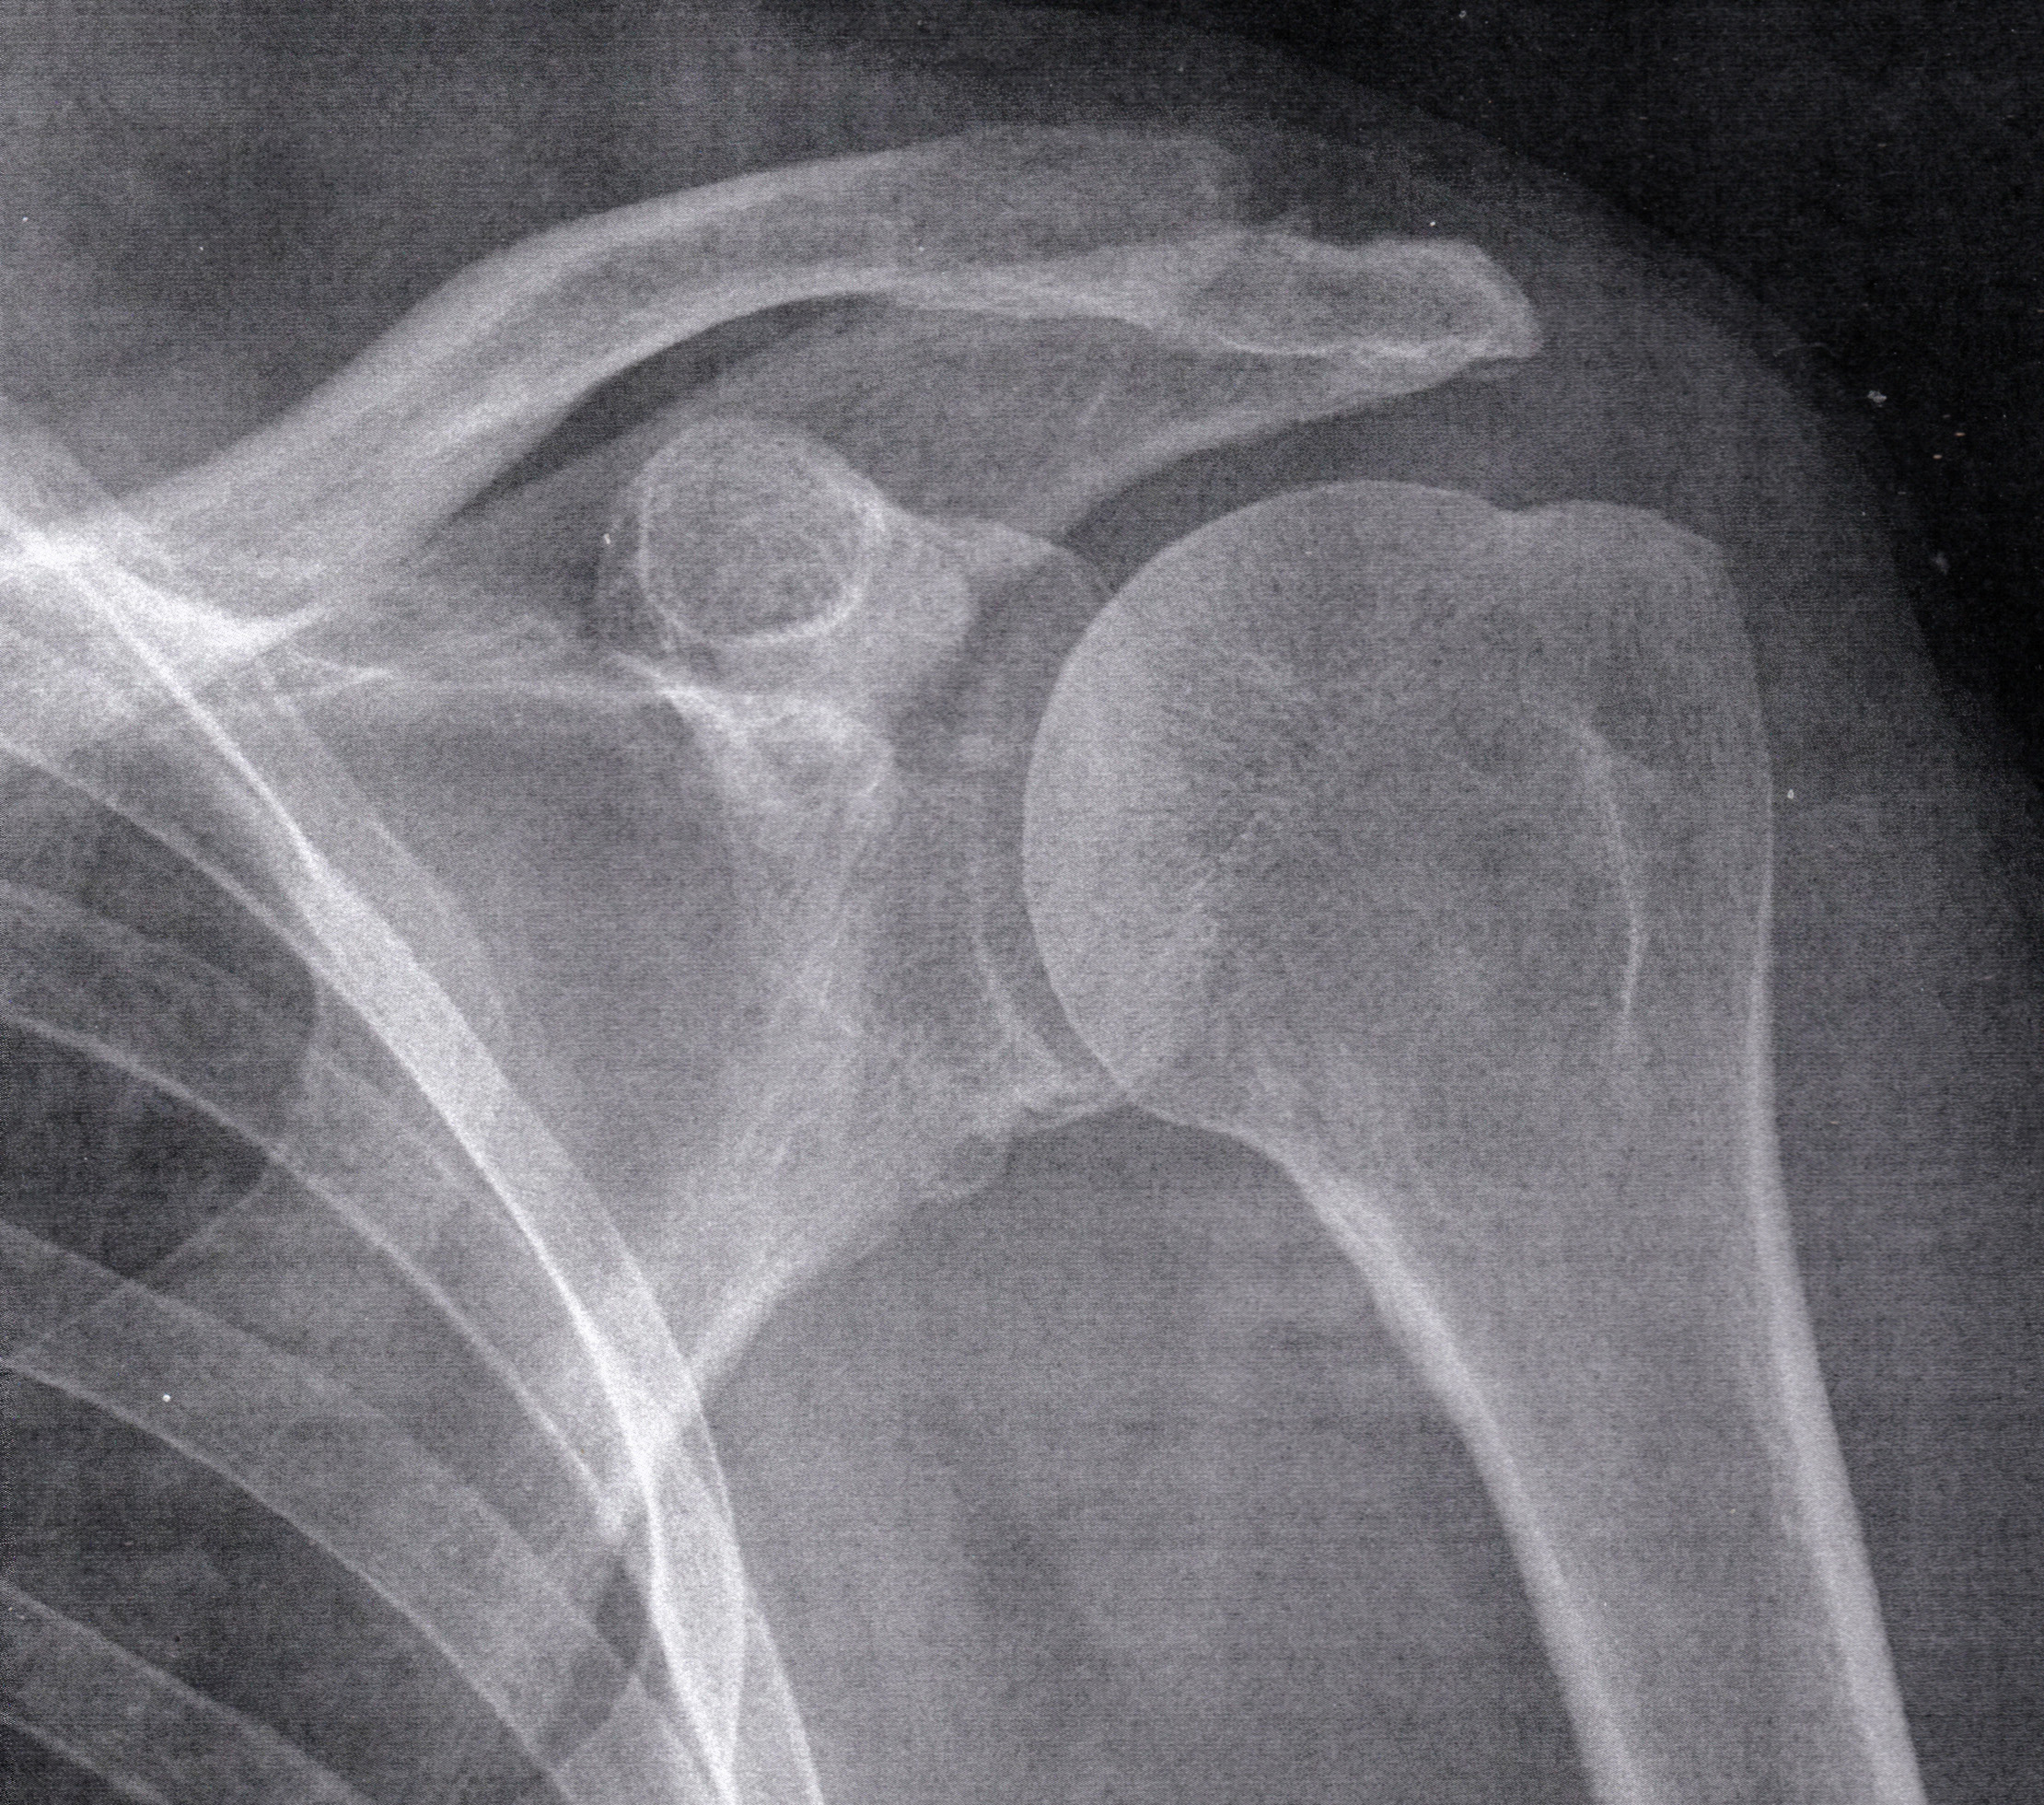

Je tady někdo doktor?

Proč mne bolí už měsíc levý ramenní kloub?

Není ta ruka vykloubena?

Mažu na to už měsíc Voltaren a bolí to furt.

Doktor nejsem, ale přidal bych k tomu ibuprofen prášek.

Až se to uklidní, tak každé ráno cvičit (různá kroužení, střihání rukama atd.), možná použít do googlu heslo rotátorová manžeta...